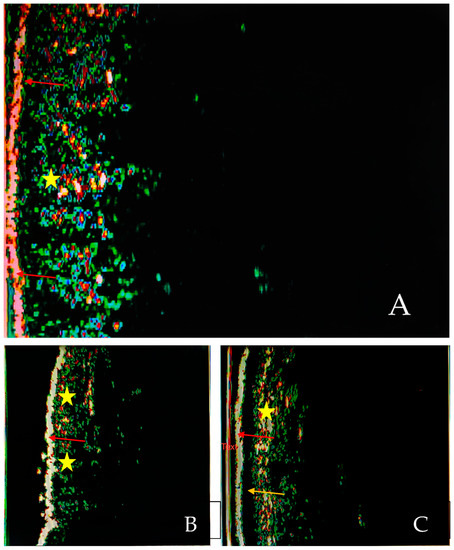

Figure 1

Objectives: Actinic keratoses (AKs) are one of the most common reasons for consultation in the elderly population. This study aimed to assess the efficacy of 5-ALA PDT in AK treatment using high-frequency ultrasonography (HFUS) to evaluate skin layer changes during therapy. Methods: In our study, we included 44 AK patients aged 53 to 89 years. All patients had lesions clinically evaluated with the Olsen and AKASI scale. HFUS imaging was performed on seemingly healthy skin and lesions before and at 4, 8, and 12 weeks of therapy. Ultrasound markers such as skin thickness, echogenicity, and pixel intensity were measured. 5-ALA was applied under occlusion for 3 h. After removing the occlusive dressing, 5-ALA was removed with a saline solution and a directed therapy with a BF-200 lamp. Full follow-ups of 56 markers of suitable quality were selected. Results: The thickness of SLEB significantly decreased in the following weeks compared to the pre-therapy results, reaching its lowest values after 12 weeks. The average pixel intensity significantly increased in each skin layer after therapy (p < 0.01). For SLEB, there were statistically significant differences in LEP, MEP and contrast. The AKASI score before and after treatment was determined for the 39 patients who underwent follow-up at week 12. The median AKASI score was 3.2 (1.2–8.6) before treatment and 0.6 (0–2.8) after. Conclusions: According to the literature data, this is the first study describing the ALA-PDT treatment efficacy in different AK severities evaluated in HFUS. HFUS provides a valuable non-invasive tool for monitoring the efficacy of PDT in AK treatment, showing significant improvements in skin texture and structure. Full article

Show Figures